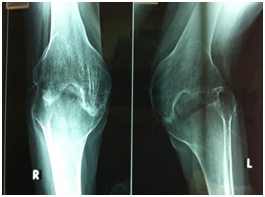

Further investigations included blood workup including inflammatory markers ESR and CRP which were normal, suggesting inactivity of the disease. Radiographs of the knee and hip joints showed bony ankylosis (Figures 2-4) with arthritis of ankle, wrist and shoulder joints and generalized osteopenia. As a part of preanaesthetic checkup chest x-ray and echocardiogram were done and found to be normal.

Figure 3 AP radiograph showing Bony Ankylosis at Tibio femoral joint.